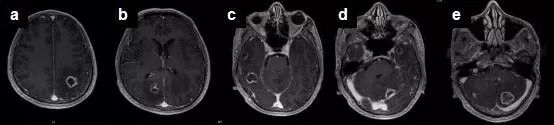

她不敢耽搁,到医院就诊,做了头部MRI(见下图)和肺部CT,提示:颅内多发占位:转移瘤?、右侧肺炎。

钟爱的头部MRI虽然报告转移瘤可能,但临床和病程演变更像是感染性疾病,结合其弓形虫抗体IgM、IgG均为阳性,故高度怀疑弓形虫脑病,即可启动了磺胺类药物的治疗,2周后复查头部MRI,提示大部分病灶已消失,小脑和左侧顶叶的病灶也明显缩小。

弓形虫脑病患者大多数血清抗弓形体抗体阳性,通过留取脑脊液标本行PCR检测弓形体基因组中一条529bp的特征性片段,其诊断灵敏度为68.8%,特异性高达100%。弓形虫脑病在影像学上特征性地表现为多发环状强化病灶,周围伴有水肿和占位效应,MRI检查较CT更为敏感。多数情况下,依据CD4+T淋巴细胞数,血清学检查,临床表现,以及特征性的影像学表现,即可拟诊TE并启动治疗,如果经验性治疗有效,便可确定诊断,仅仅在上述证据不足而导致诊断困难时才考虑开颅活检。